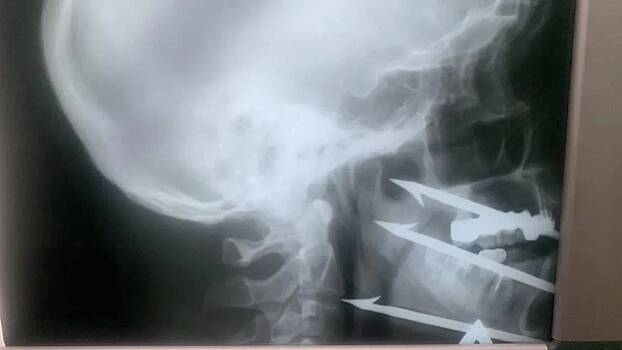

Хирурги Волгоградской городской клинической больницы № 1 спасли 52-летнего мужчину, который выстрелил себе в лицо трехзубым гарпуном во время подводной ловли рыбы. Предмет благополучно извлекли, и врачам удалось сохранить критически важные сосуды и нервы. Об этом в среду, 3 декабря, сообщили в пресс-службе Министерства здравоохранения региона.

— Ситуация была критическая: инородное тело остановилось в миллиметре от сонной артерии. Любое неосторожное движение или смещение могло привести к гибели, — говорится в сообщении.

Операцию проводили врач челюстно-лицевого отделения больницы № 1 Роман Стасюк, которого в этом году признали лучшим хирургом Волгоградской области, и сосудистый хирург больницы № 25 Олег Виноградов.